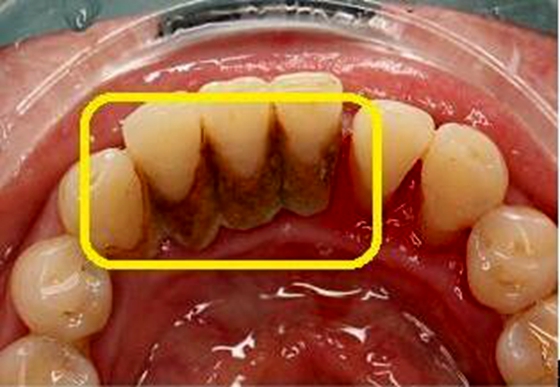

近日,张女士带着她16岁的女儿前来湘雅常德医院口腔科就诊,她焦急说到:“我女儿最近因为口臭都不愿意说话了,非常担心这样下去会被憋坏呀!”据了解,张女士在带着女儿在其他科室检查后无异常,便带着她来到了口腔科寻求解决方法。检查后发现小姑娘牙齿上覆盖了厚厚的一层牙结石,还有部分龋坏。 小姑娘进行洁牙和龋齿充填术后,开始慢慢恢复到了“话痨”状态,并表示自己回去后一定每天刷两次牙,每次刷三分钟。张女士看到女儿的变化,舒了一口气,开心地笑了!科普小知识 一、口腔异味在生活中是很常见的,最近气温升高,我们对口腔异味的“敏感度”也不断升高。那么口腔异味来自哪里呢? 口腔异味来自嘴里的特殊细菌,这些细菌在分解食物时,会产生一些副产品,称为挥发性硫化物,引起类似臭鸡蛋的气味,这是口臭的根本原因。口臭的原因还有很多,可能是“上火”、口渴、吃了味大的食物、龋齿、牙周病、牙龈炎等病理性口腔疾患;也可能是鼻窦炎、肺脓肿、糖尿病等疾病的表现,但并不是那么常见。